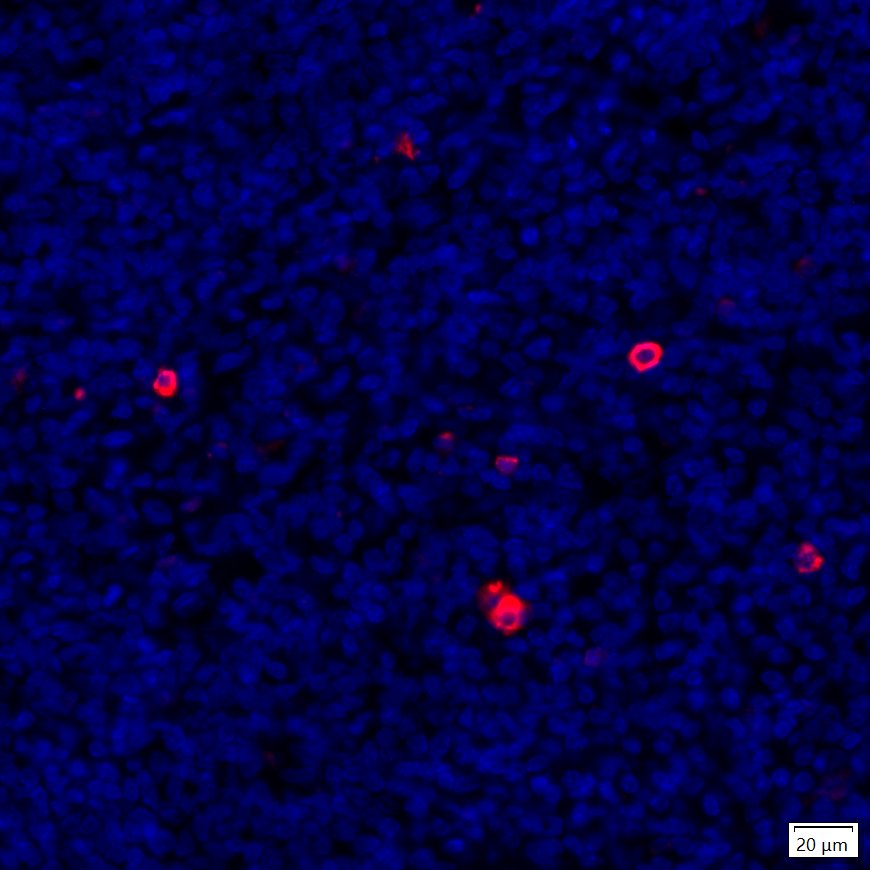

Immunocytochemistry analysis of EL4 cells labeling IL-6 with Mouse anti-IL-6 antibody (EM1701-45) at 1/1,000 dilution.

Cells were fixed in 4% paraformaldehyde for 15 minutes at room temperature, permeabilized with 0.1% Triton X-100 in PBS for 15 minutes at room temperature, then blocked with 1% BSA in 10% negative goat serum for 1 hour at room temperature. Cells were then incubated with Mouse anti-IL-6 antibody (EM1701-45) at 1/1,000 dilution in 1% BSA in PBST overnight at 4 ℃. Goat Anti-Mouse IgG H&L (iFluor™ 488, HA1125) was used as the secondary antibody at 1/1,000 dilution. PBS instead of the primary antibody was used as the secondary antibody only control. Nuclear DNA was labelled in blue with DAPI.

beta Tubulin (ET1602-4, red) was stained at 1/100 dilution overnight at +4℃. Goat Anti-Rabbit IgG H&L (iFluor™ 594, HA1122) were used as the secondary antibody at 1/1,000 dilution.